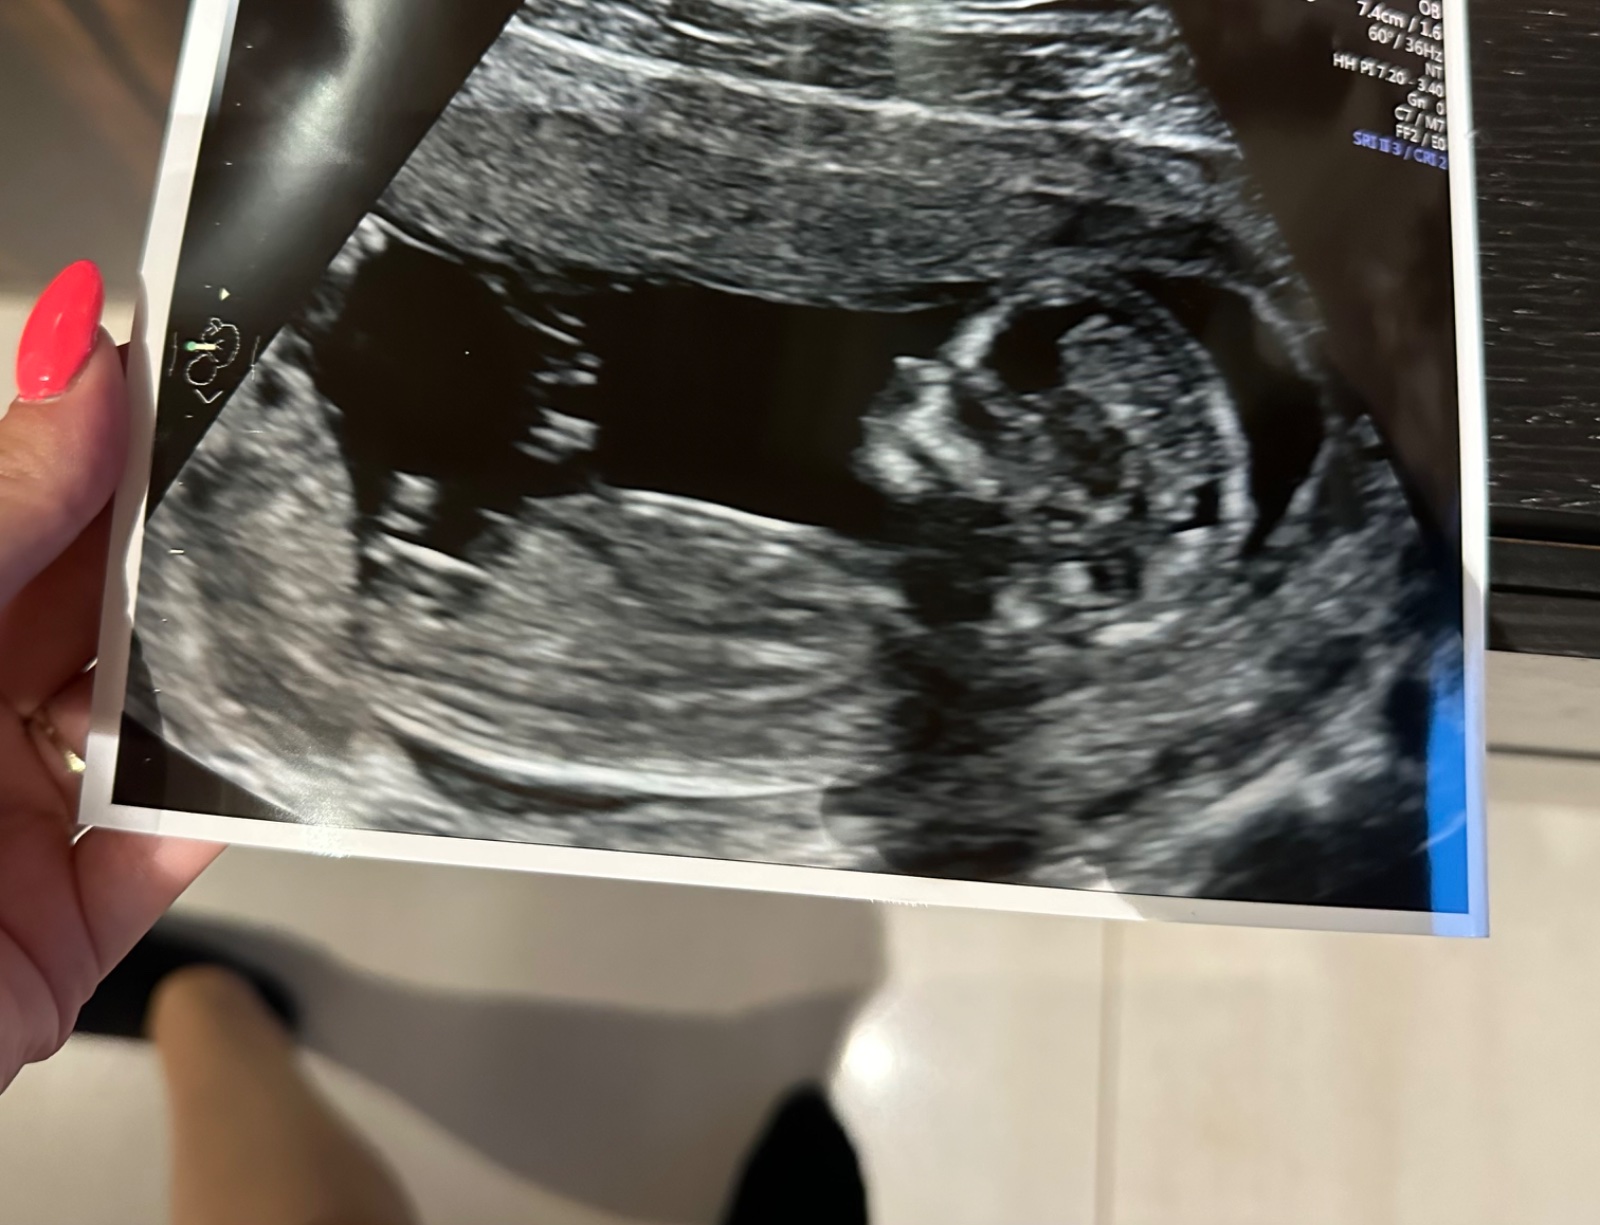

chtěla jsem se zeptat, zda je z fotky vidět pohlaví?

Myslela jsem, že to je nožička a ne pohlavní hrbolek, alenerozumím tomu🙂

z fotografie lze těžko říci, bylo by potřeba vidět "naživo". ☹